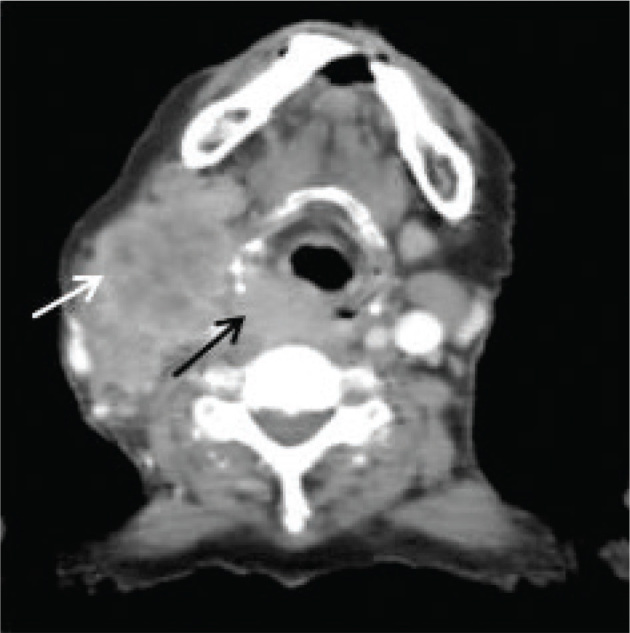

Case presentation: We report a middle-aged female patient, with known case of hypopharyngeal squamous cell carcinoma, who initially showed partial response to chemoradiotherapy but developed cutaneous nodules in the region of the right axilla and bilateral lateral chest wall posterior to the posterior axillary fold. Excision biopsy of one of these nodules showed metastatic squamous cell carcinoma. The patient was again referred to the Oncology Department of INMOL Hospital and her chemotherapy was planned for cutaneous metastasis.